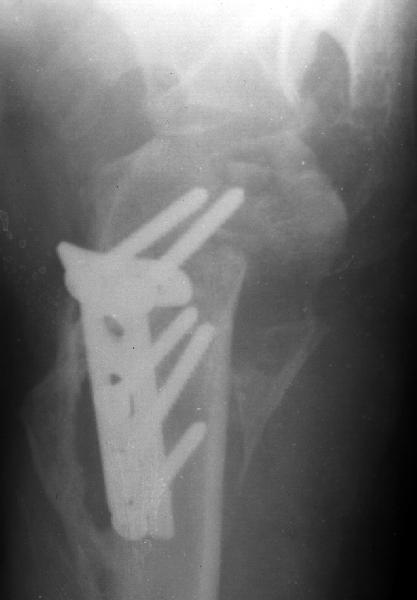

Мужчина 25 лет 16 августа 2002 г. в автоаварии получил перелом шейки плеча (снимок 1); 5 сентября в городской больнице выполнен остеосинтез пластинкой (снимок 2).К настоящему времени попал к нам на разработку ввиду выраженной контрактуры плечевого сустава. В течение последнего месяца беспокоят умеренные боли в области плечевого сустава, усиливающиеся при разработке, еще и торчит край пластинки. Нынешняя рентгенологическаякартина на снимках 3 и 4. Головка плеча уменьшается, сращение сомнительное.Кроме удаления пластинки, что еще на сегодня целесообразно сделать?Заранее спасибо.

2.Пластинка , на мой взгляд, худшее решение для перелома шейки плеча. Сама пластинка слишком груба и массивна, целая слесарня в очень чувствительной для повреждений суставе.